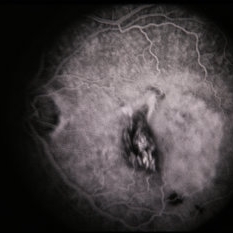

RPE Tear

RPE Tear

Sep 9 2014 by David Callanan, MD

78-year-old male, RPE tear.

Condition/keywords: retinal pigment epithelium